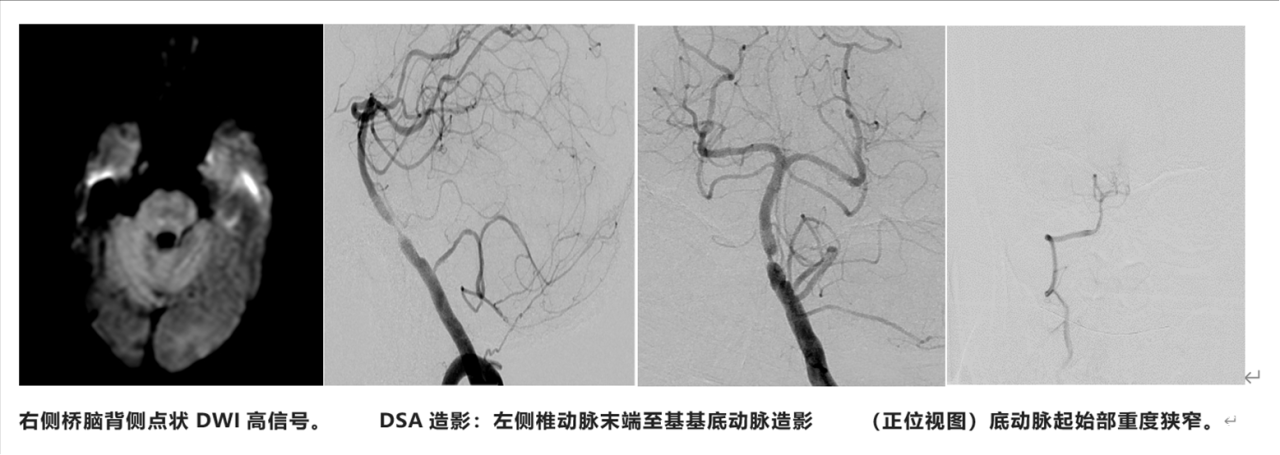

患者男性,52岁;因“头晕、视物重影、行走不稳1月”入院。活动中出现头晕、行走不稳,有视物成双,外院头颅MR检查发现左侧枕叶、右侧桥臂急性脑梗死,桥脑陈旧性病灶;MRA发现基底动脉起始部重度狭窄。予阿司匹林100mg qd+氯吡格雷75mg qd联合抗血小板,阿托伐他汀20mg qn降脂治疗。既往史:无高血压病、糖尿病、冠心病病史;吸烟20余年。

予急诊头颅CT复查未见颅内出血。在双抗基础上加用替罗非班 0.05ug/kg/min泵注维持治疗,症状逐渐改善。行急诊头颅MR+DWI见右侧桥脑背侧点状急性梗死病灶。

手术适应证:

症状性颅内大动脉狭窄,经强化药物治疗后仍有对应区域缺血事件发作。

手术风险评估:

1、入径:近端血管无串联狭窄,无近端血管迂曲成袢;

2、病变狭窄特征:80%狭窄; 斑块稳定性:MR见斑块强化,提示易损斑块;

3、病变局部穿支情况:斑块主体位于前外侧壁,局部无脊髓前动脉发出,AICA及PICA开口远离病变;

4、远端血管着陆段>5mm为局部性狭窄;

5、侧支情况:1级侧支(后交通)未开放。